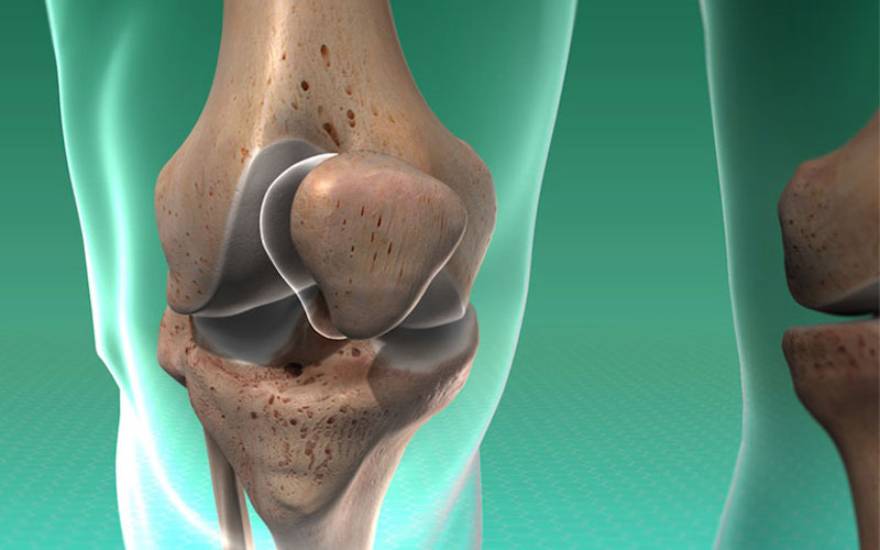

髌骨是保护膝关节前侧的重要结构,对支撑膝盖活动、实现腿部伸展弯曲及保持平衡具有关键作用。该病是指髌骨出现裂痕或碎裂成多块的重度损伤。髌骨一旦碎裂,膝关节活动能力将显著下降,引发疼痛并严重影响日常行动。

膝关节髌骨结构示意图